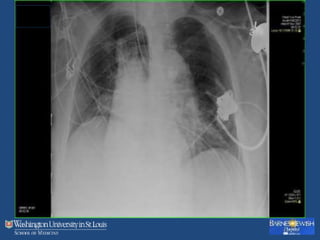

No VAP

BAL: 463 nucleated cells, 83% macrophages, no significant

growth of bacteria.

No further antibiotics, recovered.